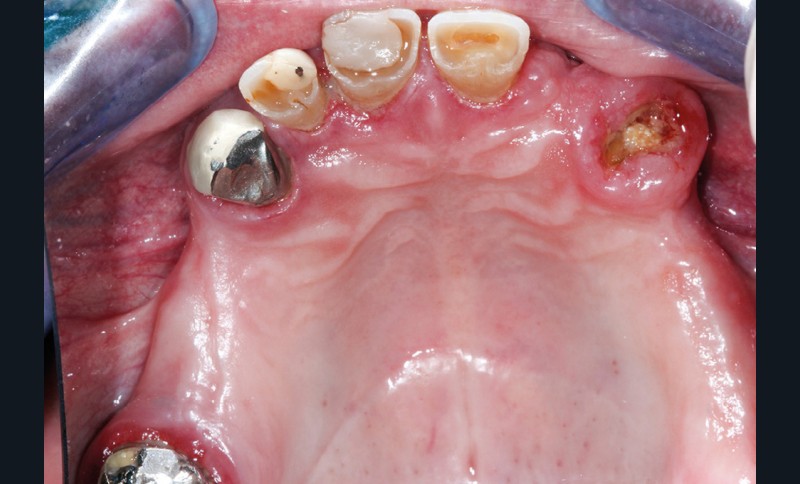

Première décision thérapeutique (janvier 2019) (fig. 1 à 3)

Après une étude prothétique [4, 5], il est décidé de procéder à l’extraction des dents maxillaires résiduelles (sauf une molaire qui servira pour enregistrer l’occlusion et qui sera avulsée dans un second temps), avec une implantation immédiate de 6 implants maxillaires et une mise en charge immédiate d’un bridge provisoire. Les implants se distribuent sur l’arcade ; des aménagements sous-sinusiens ne sont pas nécessaires (fig. 4 à 6).